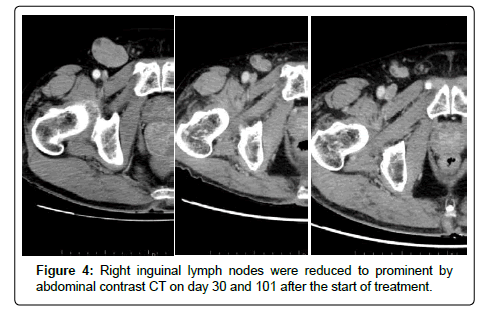

A 59-year-old male with the chief complaint of bloody stool underwent transanal tumor resection for an anorectal malignant melanoma. Rectal amputation and inguinal lymph node dissection were not performed due to severe anemia with platelet depression and poor general condition. After the operation, treatment with an immune checkpoint inhibitor was started. A gait disturbance was diagnosed as postoperative inflammatory neuropathy based on a nerve biopsy. As steroid treatment was necessary, the immune checkpoint inhibitor was discontinued after a single dose. Tissue diagnosis identified the BRAF gene mutation, and combination therapy with dabrafenib/trametinib was started. Abdominal contrast computed tomography on day 30 and 101 after the start of medication showed decreased right inguinal lymphadenopathy and a partial response (PR) was determined based on the response evaluation criteria in solid tumors (RECIST). Anorectal malignant melanoma is rare. We report a case of anorectal malignant melanoma in which dabrafenib/trametinib combination therapy was effective.

A 53-year-old male presented with a chief complaint of bloody stool. Colonoscopy showed a 3-cm type 1 tumor on the dentate line and anorectal malignant melanoma was diagnosed on biopsy (Figure 1). Abdominal computed tomography (CT) and magnetic resonance imaging showed enlarged right inguinal lymph nodes (Figure 2). No metastasis was revealed in the liver or the lungs on CT and fluorodeoxyglucose-positron emission tomography (Figure 3). Severe anemia and platelet decline were observed (hemoglobin 8.6 g/dL, platelets 30,000/dL). Rectal amputation was considered difficult due to poor general condition and platelet decline, and transanal tumor resection was performed for hemostasis. After the operation, treatment with an immune checkpoint inhibitor was started (Nivolumab 3 mg/kg). A gait disturbance was observed on postoperative day 5. The cause of the gait disturbance was diagnosed as postoperative inflammatory neuropathy on nerve biopsy, necessitating systemic steroid administration. Therefore, the immune checkpoint inhibitor was discontinued after a single dose. In addition, tissue diagnosis identified the BRAF V600E gene mutation and combination therapy with dabrafenib/trametinib was started. Steroid treatment for the inflammatory neuropathy was performed in parallel [3]. The gait disturbance improved, and the steroid was able to reduce dose. Prominent right inguinal lymphadenopathy was reduced on abdominal contrast CT on day 30 after the start of treatment, and a partial response (PR) was determined by RECIST (Figure 4). In CT of day 30, there was a possibility of the therapeutic effect of the immunity checkpoint inhibitor, although it was administered only once, furthermore, we confirmed further lymph node reduction with CT of day 101. Based on these findings, the effect of dabrafenib/ trametinib combination therapy was judged as PR. Fever of 38°C was observed on day 45 after the initiation of treatment, but responded to symptomatic therapy. There were no other obvious adverse events.